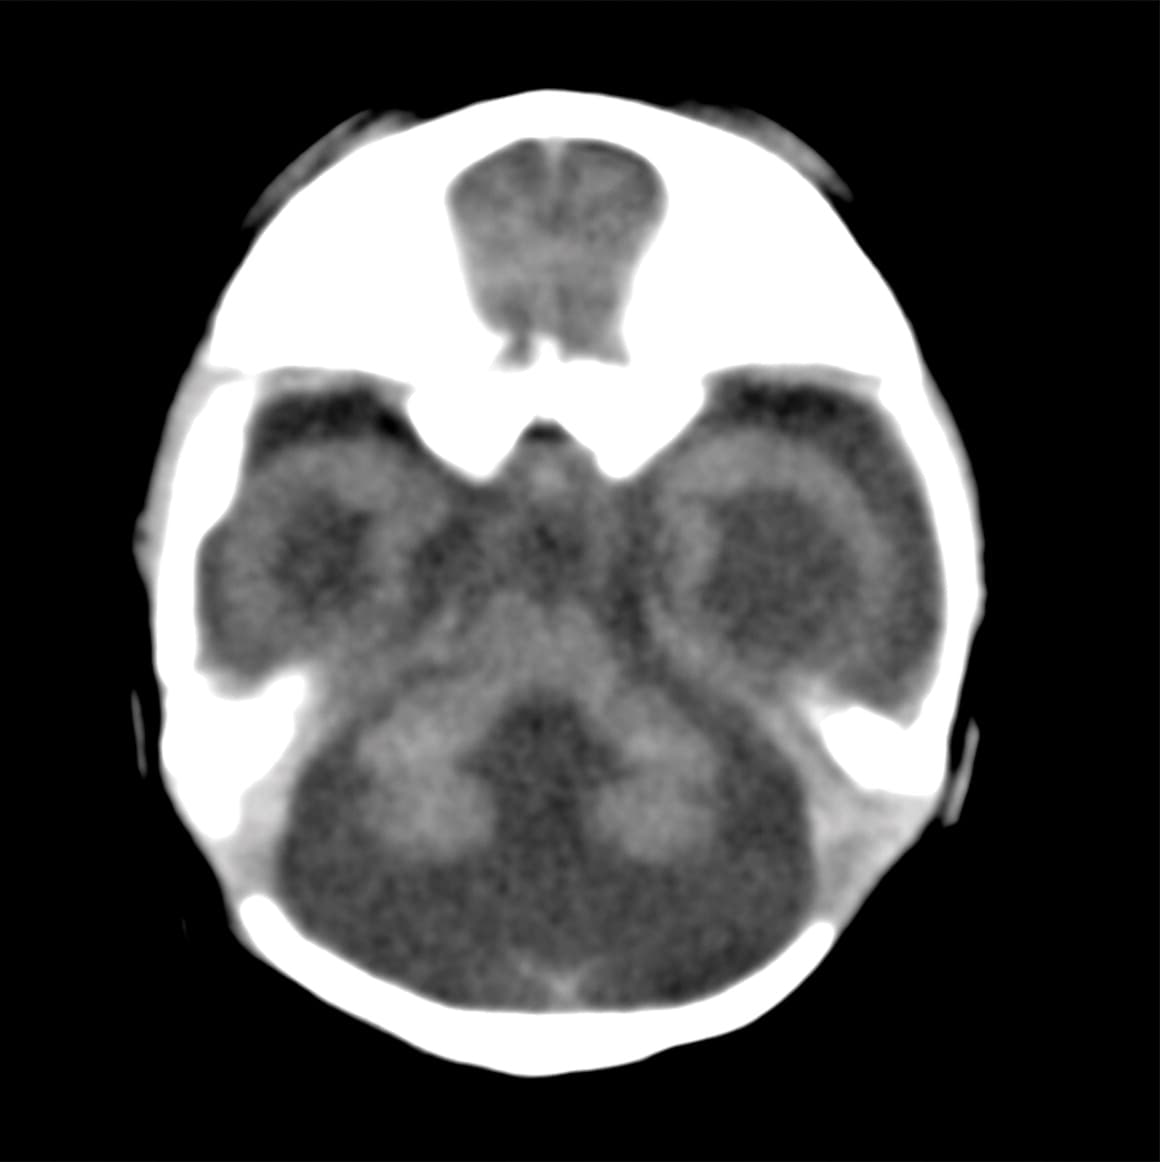

El feto falleció. Las imágenes computarizadas muestran que tenía calcificaciones en la materia blanca, el tálamo y los ganglios basales.

Radiology.

No tenía el cuerpo calloso que conecta ambos hemisferios.